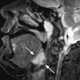

Lingual tonsil

The lingual tonsils are a collection of lymphatic tissue located in the lamina propria of the root of the tongue. This lymphatic tissue consists of the lymphatic nodules rich in cells of the immune system (immunocytes). [Source: Wikipedia ]